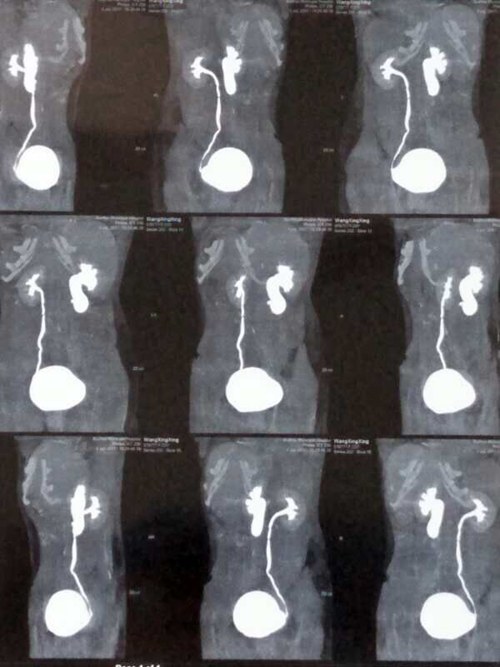

术前泌尿系CTU

患者女性,23岁,因右侧腰背部间断性胀痛不适3年多,曾在当地医院行相关检查被告知无法手术后,经多方打听来我院泌尿外科就诊。李朝明主任组织科室医生仔细了解、研究患者病情,制定详尽的诊疗方案,完善术前检查后于10月31日进行手术,术中发现右侧输尿管于下腔静脉后方斜行穿过,周围纤维条索形成,造成输尿管成角畸形并下腔静脉压迫狭窄,手术难度极高,李朝明主任仔细游离下腔静脉周围组织,直至下腔静脉骨骼化,充分暴露下腔静脉后方输尿管,切除输尿管狭窄段后行肾盂输尿管成形术,手术历时3小时,顺利完成。术后患者经医护人员的精心护理和治疗,病情稳定、恢复良好。